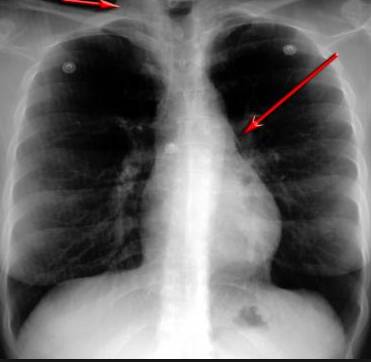

并且,因?yàn)楹粑到y(tǒng)結(jié)構(gòu)復(fù)雜,在體檢時(shí)醫(yī)生很難通過(guò)一種檢測(cè)手段,判定早期患者的病情。

使用這臺(tái)掃描儀,將直接把器官變成3D圖形!細(xì)微的毛細(xì)血管,幾毫米大的肺泡和支氣管,都將能看的一清二楚!

你的每一個(gè)氣泡,每一段支氣管,哪兒有病變都清清楚楚的將展示在醫(yī)生面前!

沒(méi)有這項(xiàng)新技術(shù),醫(yī)生在做體檢的時(shí)候,很難通過(guò)一種測(cè)試斷定一個(gè)人是否有呼吸系統(tǒng)疾病。

可是現(xiàn)在他們不但能看到整個(gè)肺部的3維結(jié)構(gòu)圖。還能看到空氣進(jìn)入人體后的所有微小變動(dòng)!